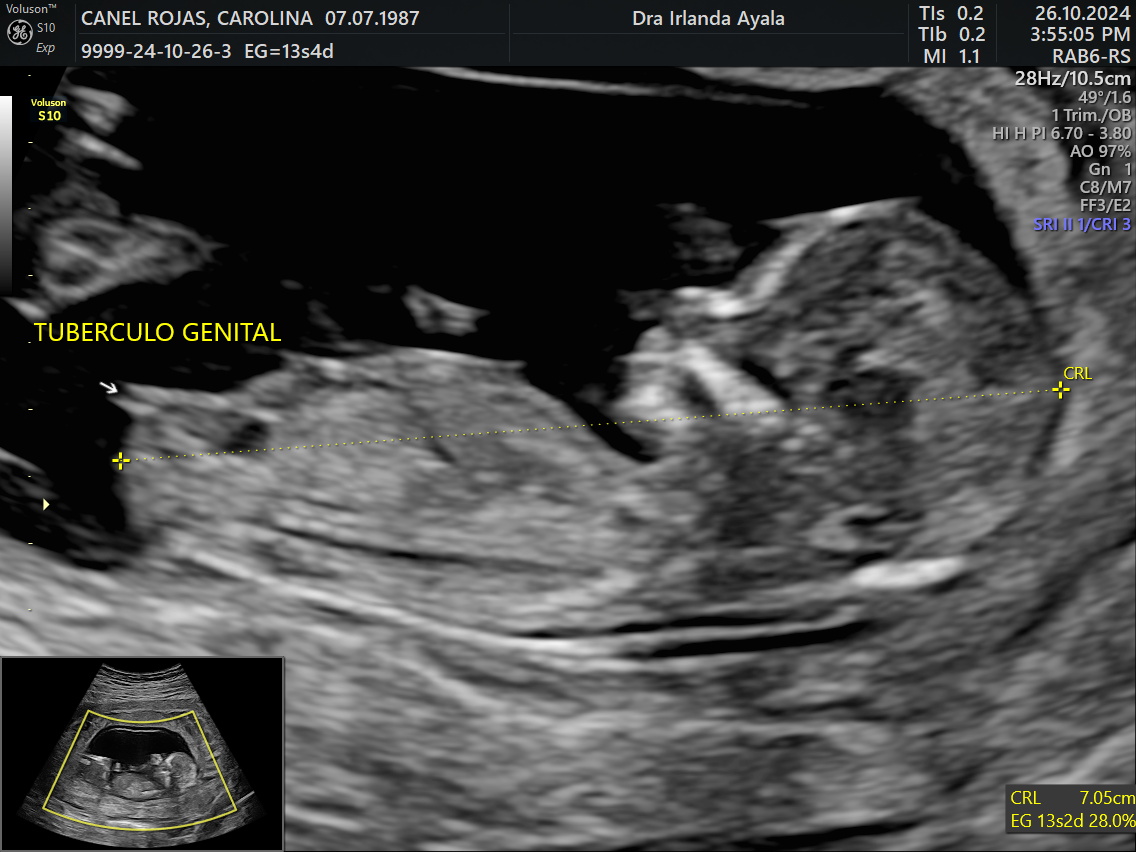

Galería de recuerdos felices Las primeras fotos de Ambar y la historia de sus papás-